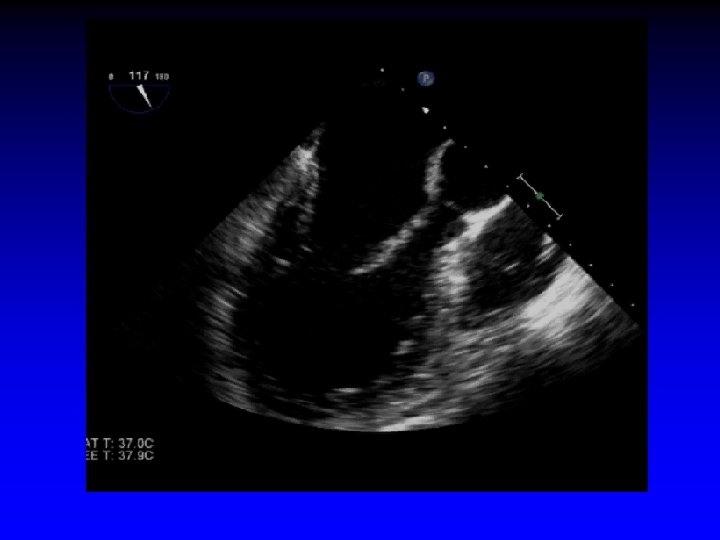

6. Leaflet Grasping Echo Guidance • Advance clip into LV just below the leaflet edges prior to grasping • Grip arms placed in grasping position (approximately 120º) • Pull back during systole to capture leaflets Midesophageal long-axis view

5. Advancing Mitra. Clip into LV • Imaged best with X-plane imaging (intercommissural view and LVOT view) • Reassess orientation of clip (Clip may rotate during “dive” into LV) • Look for: - Perpendicular alignment to coaptation line - Both leaflets moving freely above clip arms

6. Assessment of Leaflet Capture Echo Guidance • Clip partially closed to secure insertion of leaflets into the clip • Carefully assess the grasp leaflets: - Adequacy of leaflet insertion - Resultant degree of MR